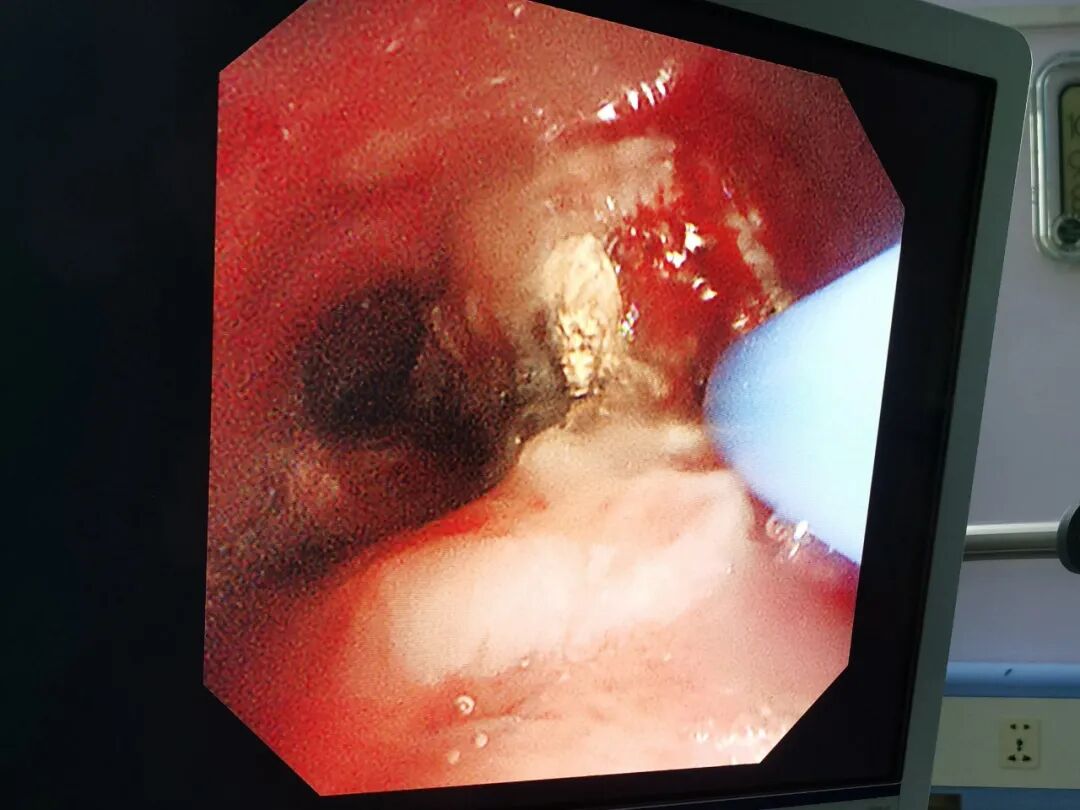

据了解,患者为中年男性,因“诊断肺癌7月余,咳嗽、气促4天”入院到肿瘤血液科治疗,完善检查后诊断为“右肺鳞状细胞癌”。因肺部鳞癌阻塞双侧主支气管,患者出现气促明显,血氧下降,在紧急处理后症状有所缓解,但要真正解决患者的呼吸问题,需要切除阻塞气道的肿物。呼吸与危重症医学二科呼吸介入团队与麻醉团队、肿瘤血液科团队紧密配合,呼吸与危重症医学二科副主任医师钟如柱为第一术者,为患者行“硬质支气管镜联合电子支气管镜气道肿瘤切除术”,在硬质支气管镜下解除左主支气管梗阻,术后患者气促症状明显缓解,生活质量得到改善,手术为患者下一步治疗创造了条件。

术中